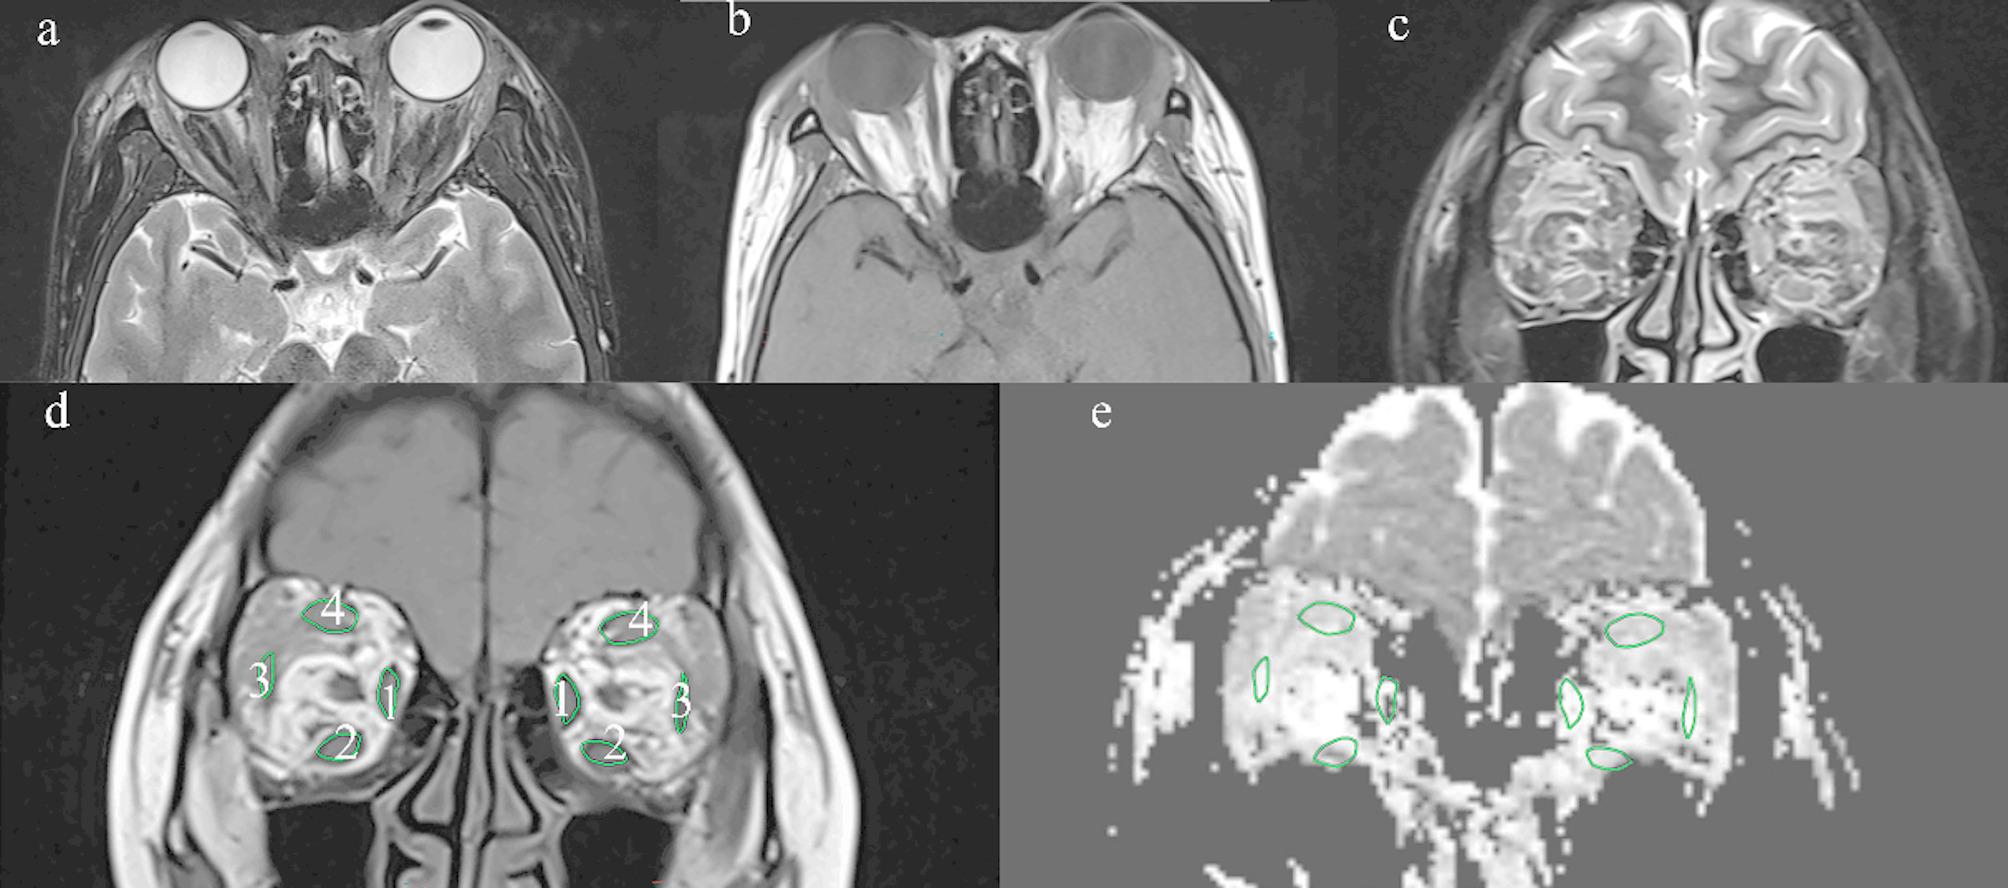

Method: Eighteen active and moderate-to-severe bilateral TED patients (responsive group, n = 8 patients (16 eyes); unresponsive group, n = 10 patients (20 eyes)) who underwent orbital long variable echo‑trains (Resolve)-diffusion tensor imaging (DTI) before GC therapy were retrospectively enrolled. The ADC values of each EOM were collected. The correlation between the ADC of EOMs and the efficacy of GC therapy was analyzed.

Results: Age was significantly younger in the responsive group compared with the unresponsive group (52.13 ± 5.18 years vs. 58.80 ± 9.33 years, P value = 0.02).There were no statistical differences in sex, smoking, TED duration, visual acuity, intraocular pressure, exophthalmos, clinical activity score, the levels of free triiodothyronine, free tetraiodothyronine thyroid-stimulating hormone, and thyroid-stimulating hormone receptor antibody between the responsive group and the unresponsive group. Apparent diffusion coefficient in the responsive group were significantly lower than that in the unresponsive group in superior rectus muscle (1351.17 ± 232.12 vs. 1624.36 ± 193.70, P value = 0.001) and medial rectus muscle (1420.69 ± 192.05 vs. 1697.00 ± 199.89, P value = 0.001). After age, sex and CAS adjustment, ADC of the superior rectus muscle and medial rectus muscle were independent predictors of the response to GC treatment by binary logistic regression analysis. The cut-off value of ADC was 1582.00 × 10- 3 mm2/s in superior rectus muscle with a sensitivity of 88% and a specificity of 65% respectively [ area under the curve (AUC) = 0.81]. The cut-off value of ADC was 1541.39 × 10- 3 mm2/s in medial rectus muscle with a sensitivity of 75% and a specificity of 80% (AUC = 0.84). There were no significant difference in the predictive efficacy between the two ADC cut-off values.

Conclusions: Apparent diffusion coefficient values of EOMs from resolve DTI can be used as an indicator to predict the efficacy of GC therapy. Moderate-to-severe active TED patients with low ADC values at baseline in superior rectus muscle or medial rectus muscle may respond well to GC therapy.